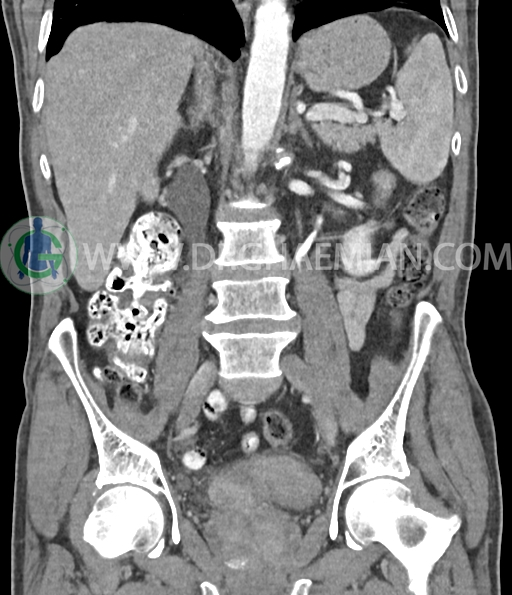

در سی تی اسکن اسپیرال شکم و لگن با و بدون کنتراست خوراکی و وریدی (مولتی دیدکتور 16 با مقاطع ظریف و بازسازی های ساژیتال و کرونال) :

ضایعه ای در کیسه صفرا، مجاری صفراوی، طحال، کلیه چپ ، پانکراس و آدرنالها مشهود نیست مایع آزاد در حفره شکم و لگن رویت نمی شود.

ضایعه کبدی هیپودنس بسیار کوچک به قطر 6mm در سگمان 7 لوب راست کبد مشهود است که با توجه به سایز بسیار کوچک ان در سی تی اسکن به خوبی کارکتریزه نمی شود.

دیورتیکولوز خفیف پراکنده بیشتر در کولون نزولی رویت شد.

کیست کورتیکال به قطر 15mm در پل تحتانی کلیه چپ دیده می شود.

کلسیفیکاسیون دیواره ائورت مشهود است.

پروستات با دیامتر عرضی 60mmبزرگ تر از نرمال، همراه با bulging لوب مدین به کف مثانه رویت شد.

افزایش ضخامت جداری مثانه مشهود است.

افزایش ضخامت جداری و نامنظمی و لوبولاسیون همراه باenhancement مطرح کننده انفیلتراسیون و ضایعات تومورال در سمت راست ناحیه ترایگون و دیواره لترال راست مثانه دیده می شود که باعث اتساع حالب راست و هیدرونفروز moderate در کلیه راست شده است . این یافته های می توانند مطرح کننده TCC باشند .fat stranding در اطراف مثانه مشهود است. بیرون زدگی توده مانند به قطر 18mm در سمت راست ناحیه ترایگون دیده می شود که می تواند مطرح کننده گسترش اکسترا وزیکولر تومور باشد . لنفادنوپاتی با SAD=10mm درlevel ایلیاک داخلی چپ رویت شد . لنف نود دیگر با SAD= 5mm در همین ناحیه مشهود است. با توجه به این یافته ها stage احتمالی تومور T3، N1 or N2 می باشد .